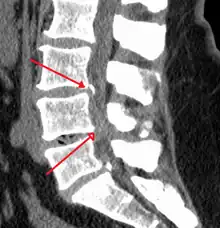

The diagnosis of spinal stenosis involves a complete evaluation of the spine. The process usually begins with a medical history and physical examination. X-ray and MRI scans are typically used to determine the extent and location of the nerve compression.

MRI

MRI has become the most frequently used study to diagnose spinal stenosis. The MRI uses electromagnetic signals to produce images of the spine. MRIs are helpful because they show more structures, including nerves, muscles, and ligaments, than seen on X-rays or CT scans. MRIs are helpful at showing exactly what is causing spinal nerve compression.

CT myelogram

A spinal tap is performed in the low back with dye injected into the spinal fluid. X-Rays are performed followed by a CT scan of the spine to help see narrowing of the spinal canal. This is a very effective study in cases of lateral recess stenosis. It is also necessary for patients in which MRI is contraindicated, such as those with implanted pacemakers.